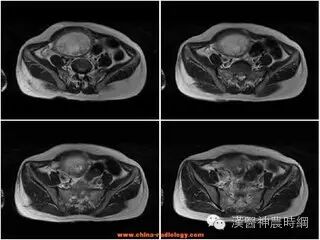

葡萄胎的水泡样组织已超过子宫腔范围,侵入子宫肌层深部或在其他部位发生转移者,称为恶性葡萄胎。发生的机会为5%~20%的葡萄胎恶变成恶性葡萄胎或绒毛膜癌,多数在葡萄胎清除后6个月内发生,但亦有葡萄胎未排出之前就发生恶变者。恶性葡萄胎虽具有恶性肿瘤特点,但治疗效果及预后均较绒毛膜癌为好。

恶性葡萄胎的主要症状是在葡萄胎排出后数月之内,出现不规则阴道流血,量多少不定,子宫略大而软,如发生子宫穿孔,有腹痛,内出血,甚至休克,葡萄胎转移到肺部可有咳血;转移到脑部则出现及溢血症状,甚至立即死亡;转移到肠可以引起消化道出血;转移到外阴,阴道和子宫颈,局部有此蓝色结节,结节破溃可造成大出血。